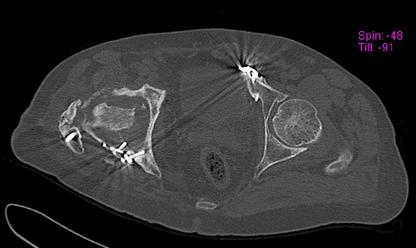

Пациент 49 лет, паровозная травма 23.2.2006, получил вертикальная

нестабильное повреждение таза, разрыв левого крестцово-подвздошного

сочленения, перелом лонной, седалищной костей слева, T-образный

оскольчатый перелом правой вертлужной впадины с переломом заднего

края, вывих правого бедра, посттравматическая пояснично-крестцовая

плексопатия с обеих сторон, паралич мышц правой голени.

В день травмы - вправление вывиха, скелетное вытяжение, 14.3.2006

чрескостный остеосинтез таза. 20.4.2006 остеосинтез правой вертлужной

впадины пластинами, осложнившийся нагноением межмышечной гематомы

правой ягодичной области. Получал консервативное лечение, было

достигнуто полное заживление раны. 24.7.2006 введены илиосакральные

винты слева. С декабря 2006 года и по настоящее время ходит на

костылях без опоры на правую ногу. Планируется THA. Помогите

определиться с вариантом костной пластики? И какую укрепляющую

конструкцию использовать?